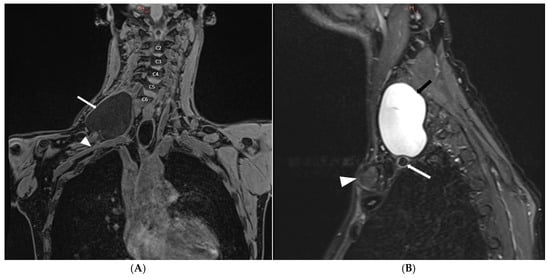

3. Case Report